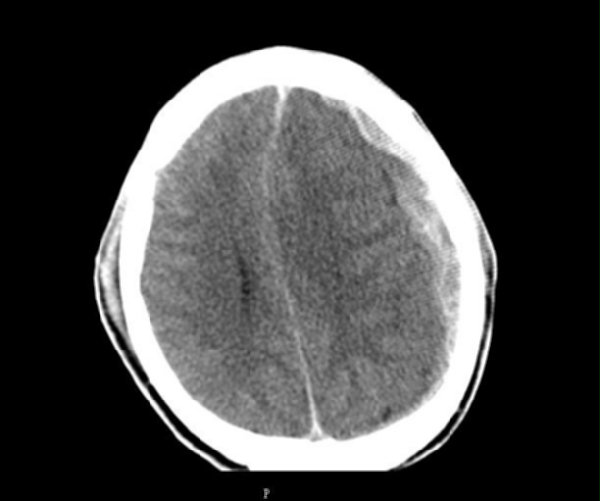

f_678122_1.jpg